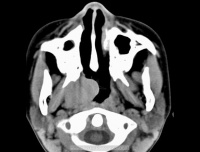

9.腹部B超CT扫描、MRI及胃肠钡餐透视等。

恶性淋巴瘤大多首先侵犯表浅和 / 或纵隔、腹膜后、肠系膜淋巴结,少数可原发于结外器官。 较多的患者在早期表现为无痛的颈部淋巴结肿大,以后其他部位的亦陆续发现。淋巴结从黄豆大到枣大,中等硬度,坚韧,均匀,丰满。一般与皮肤无粘连,在初期和中期互不融合,可活动。到了后期淋巴结可长到很大。可互相融合。

纵隔也是好发部位之一,受侵的纵隔淋巴结,可以是单个的淋巴结肿大,也可以是多个淋巴结融合成巨块,外缘呈波浪状,侵犯一侧或双侧纵隔,以后者较多见。

恶性淋巴瘤约 2% 左右可发生于肺部,表现为肺野内边界清楚的圆形或分叶状阴影,患者自觉症状很少。有的患者可侵犯肺门或纵隔淋巴结,一般很少有上腔静脉压迫征或纵隔肌麻痹,治疗预后也较好。由纵隔侵犯肺部的恶性淋巴瘤多靠近肺门,常常连成一片,可为单侧或双侧性,并常伴有气管旁淋巴结肿大,也易引起压迫症状,其预后不如原发于肺的病例。